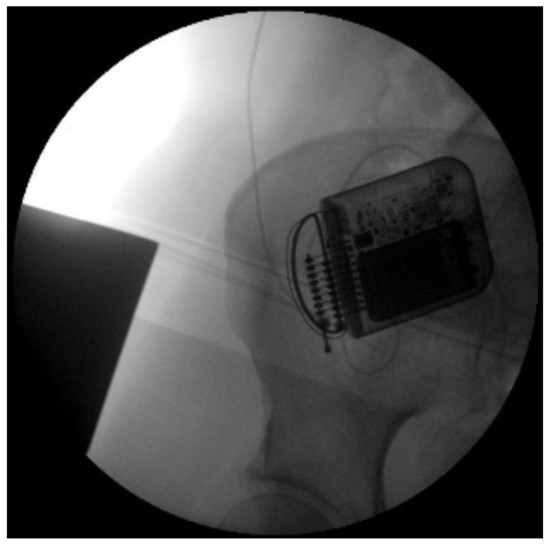

- -

2. First Clinical Evaluation and Background

3. Case Presentation